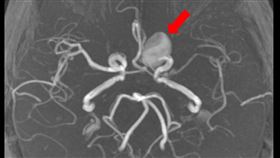

劇烈頭痛竟是腦出血!醫不開顱也能救她命

現代人壓力大,不少人有頭痛的困擾,有的人貪方便習慣一...